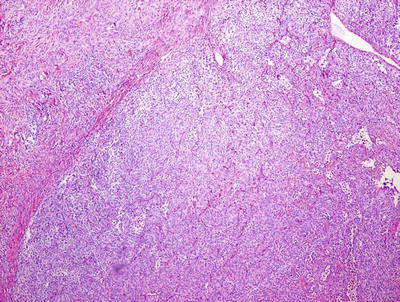

In rare cases, one may encounter nodules of melanocytes in which there is an apparent lack of maturation, and the cells appear remarkably clonal (Figs. 20.27 and 20.28). These are proliferative nodules , and require more careful histologic examination. In general, these are areas that at low magnification demonstrate increased cellular density and lack of maturation as well as increased mitotic activity, but no atypical mitoses [85] (Fig. 20.29). Necrosis is also not a feature of benign proliferative nodules, and in many cases, there is a smooth transition from the surrounding dermal nevus components to the proliferative nodule [86] (Fig. 20.28). Some authors have suggested that the absence of destructive expansile growth is another feature that distinguishes a benign proliferative nodule from melanoma [87].

Fig. 20.27

A proliferative nodule is easily observed at low magnification as a clearly demarcated nodule of melanocytes with increased cellularity and lack of maturation

Fig. 20.28

Proliferative nodules are clearly demarcated from the surrounding dermal melanocytes